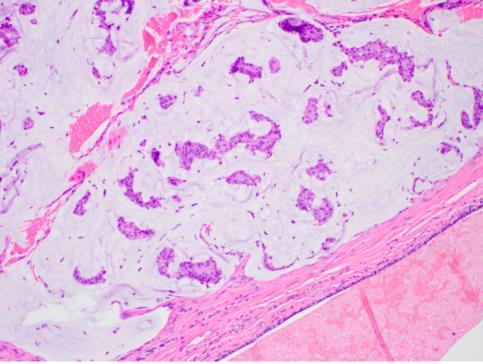

• Syringocystadenoma papilliferum

• Benign apocrine neoplasm

• Isolated or in association with naevus sebaceous

• Endophytic crateriform proliferation with papillary architecture